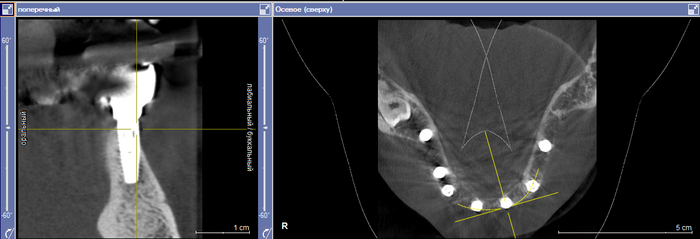

Устройство Dimoveo помещается на колено, а наночастицы, содержащиеся в физиологическом растворе, вводятся в место операции (Фото: предоставлено)

Запатентованное решение компании Dimoveo заключается в частичном повторном открытии хирургического участка и заполнении области физиологическим раствором, содержащим наночастицы железа. Затем наночастицы подвергаются воздействию ультразвуковых волн, заставляя их вращаться на высокой скорости, чтобы разрушить биопленку и дать возможность лечить инфекцию антибиотиками.

Димовео пока сосредоточен на имплантатах колена. Но Рамот говорит, что процедура подходит для любого вида замены суставов, например, колена, бедра, лодыжки, плеча и позвоночника, а также переломов костей, требующих установки винтов или пластины.